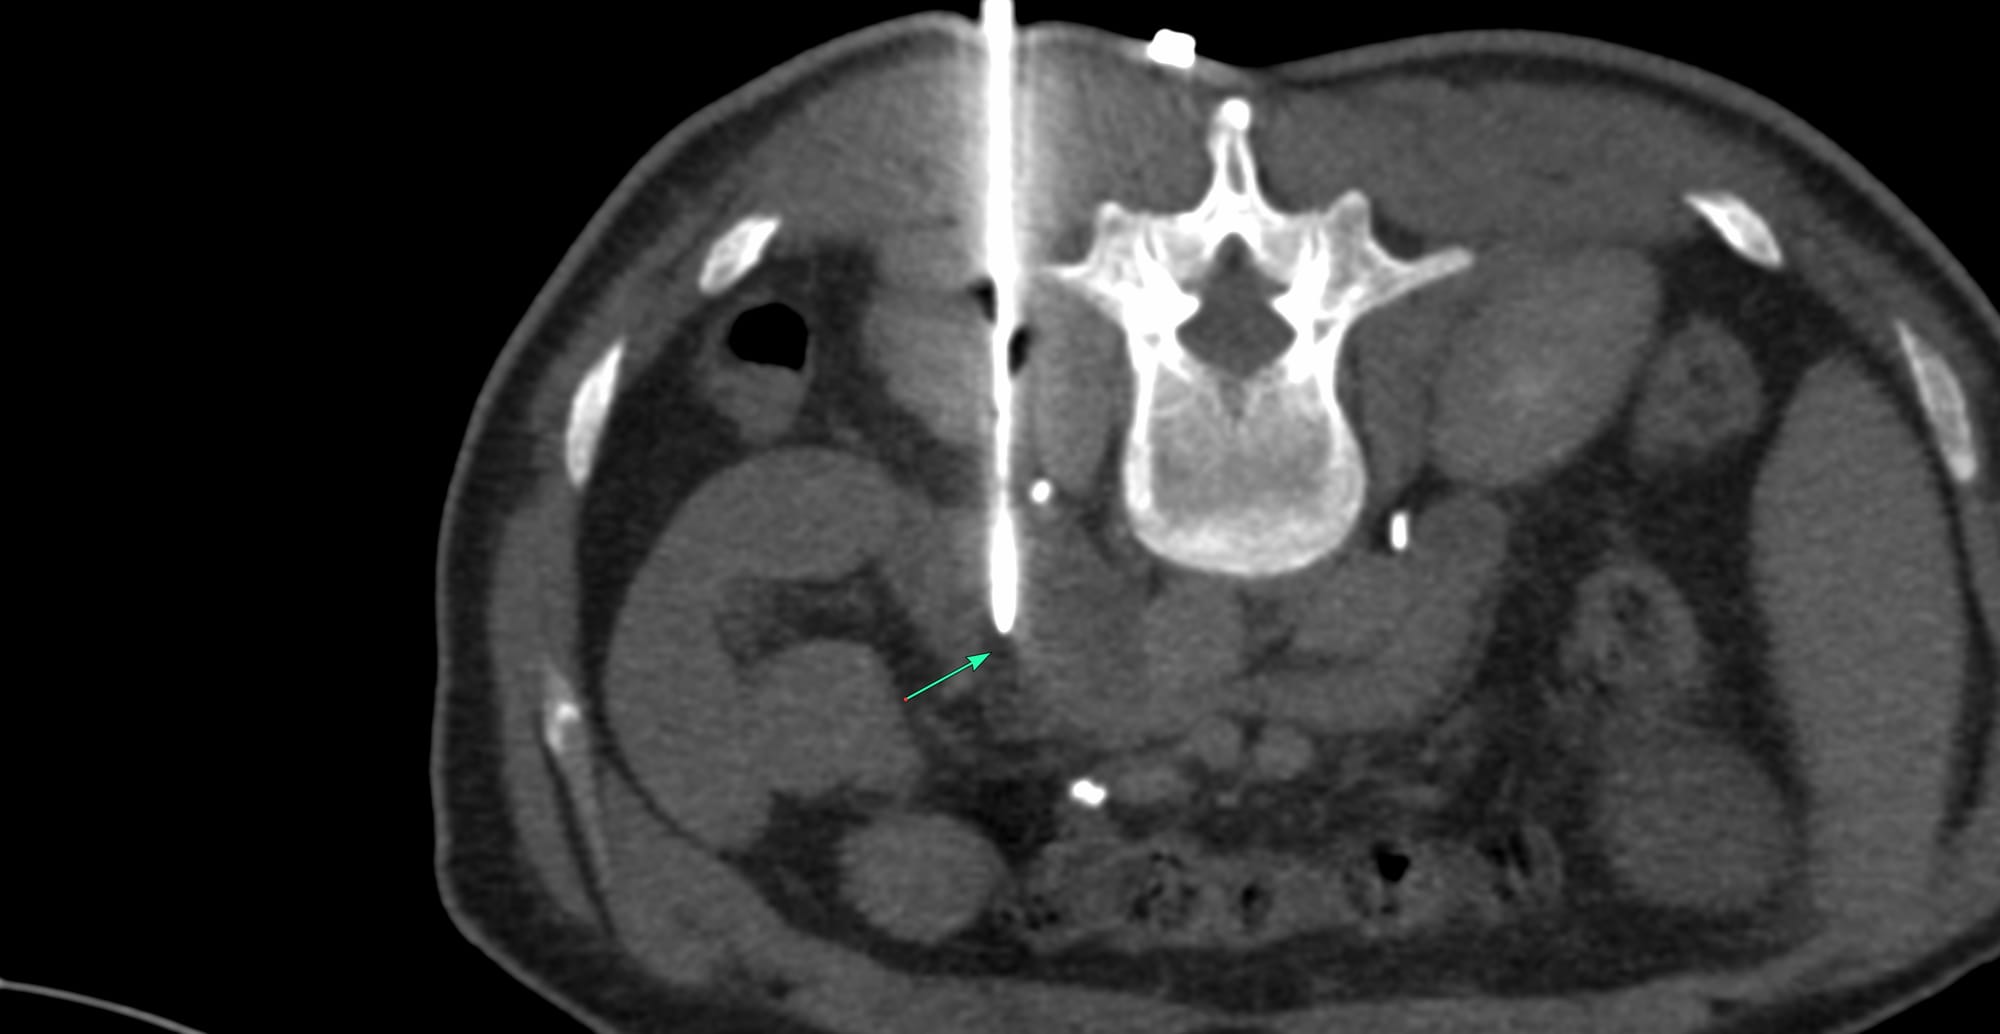

Case 172 - Right Adrenal Gland Biopsy Using an Ipsilateral Up Approach with Hydrodissection

Bhavin Jankharia - 31 December 2025